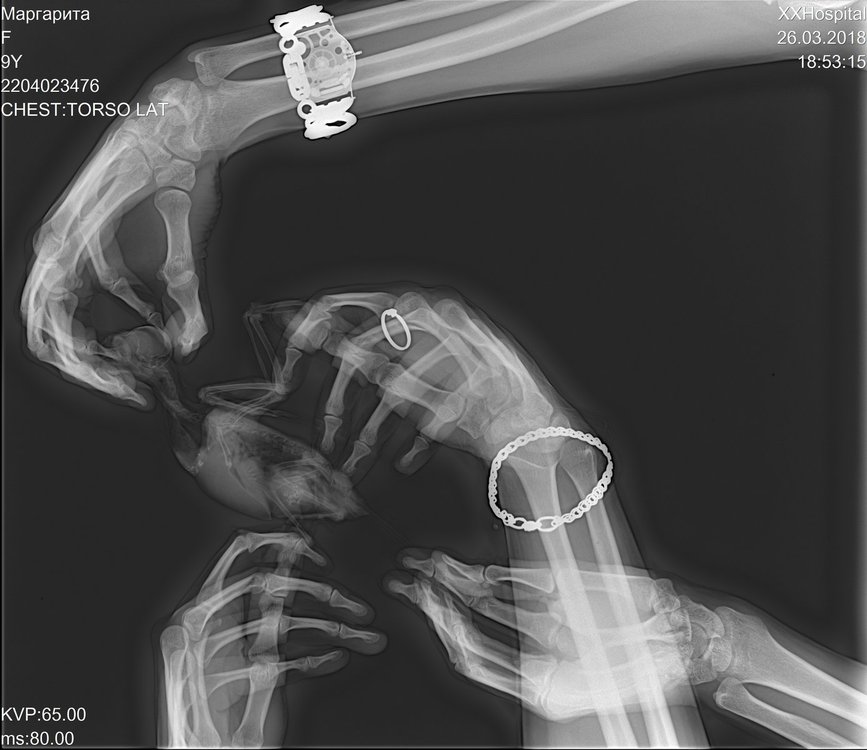

OlgaVoevodina Опубликовано 26 марта, 2018 #94 Опубликовано 26 марта, 2018 Здравствуйте, сегодня ходили на рентген. Корелла, 9 лет. Продолжительное время был синусит, долго лечили. Недавно обнаружили вздутые воздуховодные мешки, решили отвести на осмотр. Врач поставила диагноз грибковая пневмония. Сказала, в худшем случае - аспергиллез. Сказали, взять анализы крови, смывов на бак посев, микологию и цитологию. А так же бронхоскопия/целиоскопия. Но все это под наркозом, в два этапа...Подскажите, пожалуйста, как кореллы переносят наркоз? Птица активная, но чихает, воздуховодные мешки и глазки опухшие. Прилагаю фото рентгена.